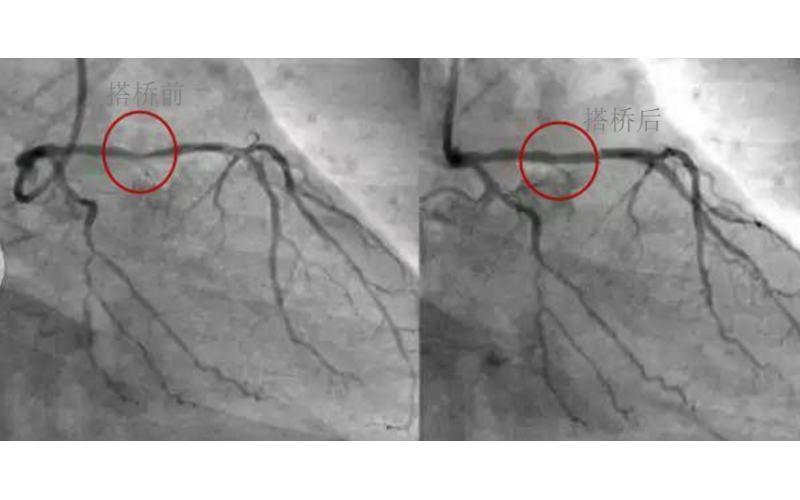

深圳市模具廠對(duì)心臟支架的關(guān)注,國(guó)產(chǎn)化的道路有多長(zhǎng)?